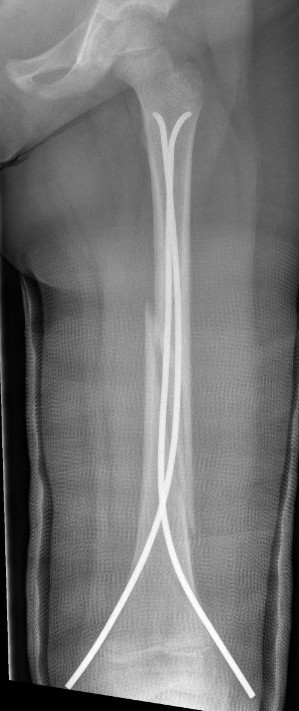

Flexible nails / Titantium Elastic Nails

Indications

Length stable fractures i.e simple transverse, short oblique

Midshaft fractures

Maximum weight up to 50 kg / 12 years old

Flexible nail technique

Wires

- available 1. 5 mm - 4.0 mm

- 30 - 40% of diameter of diaphyseal medullary canal

- i.e. if canal 10 mm wide, use 2 x 4 mm

- recommend using 2 wires same diameter to avoid rotational instability

Entry points

- medial and lateral insertion

- 1 - 2 cm proximal to distal femoral physis

- oblique entry with awl in direction of nail insertion

- can open with drill bit

- beware proximity of the femoral artery medially

- entry points should be symmetrical

Wire passage

- bend wire for 3 point fixation with bend at fracture site

- also bend the tip of the wire

- can use F Tool to reduce fracture / sheet in groin

- may need small incision and open reduction

- medial entry wire will pass into femoral neck

- lateral wire will pass into greater trochanter / medial wire into femoral neck

- use designated TEN wire cutter to cut wires

- cut off, tap in slightly further, leave 1.5 cm out so can retrieve

- wires that are too prominent can cause bursa / limit flexion / pain / protrude through skin